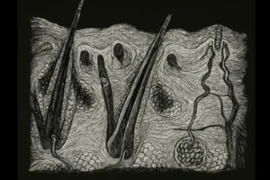

• Imaging artifacts in ultrasonography